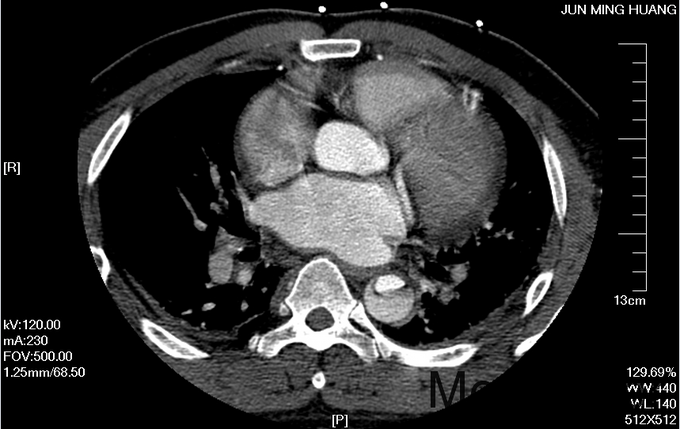

入院查体:体温36.5℃,脉搏90次/分,规则,呼吸18次/分,规则,血压150/80mmHg,胸廓正常,无胸骨叩痛。呼吸运动正常,语颤正常,无胸膜摩擦感,无皮下捻发感,叩诊正常清音,肺下界正常,双肺呼吸音粗,呼吸音对称,无罗音。心音可,心率90次/分,无杂音,腹部无压痛,无反跳痛,肝肋下未及,胆囊无压痛,Murphy征阴性,脾肋下未及,肾区无叩痛,双下肢不肿。入院后完善相关检查(胸腹主动脉CTA:主动脉夹层动脉瘤;两侧胸腔少量积液。)

予以诊断:1.主动脉夹层动脉瘤;2.高血压3级,极高危组。诊断明确后行“左颈总动脉-腋动脉转流手术+胸主动脉覆膜支架腔内隔绝术”。左侧颈部切口,游离出左侧颈总动脉,左侧锁骨下动脉,左侧椎动脉等分支。使用8mmG-tex血管一端与左锁骨下动脉行端侧吻合,G-tex血管另一端与左侧颈总动脉行端侧吻合。经右侧股动脉入路造影见主动脉夹层,破口位于左锁骨下动脉开口医院0.5cm处。左锁骨下动脉近端封闭,桥血管通畅,腋动脉及左侧椎动脉血流良好。置入美敦力胸主动脉覆膜支架(28*157mm),定位后释放。造影见胸主动脉支架释放良好。

主动脉夹层为大血管急诊,B型主动脉夹层相对预后良好。保守治疗效果尚可,近期死亡率相对不高。但对于年轻患者,我们积极治疗。患者B型主动脉夹层,破口位于锁骨下动脉附近。拟行腔内修复术。但患者破口离锁骨下动脉较近,若直接封闭,可影响左上肢活动及椎动脉顺行血流。故根据患者情况行一期复合手术(即“左颈总动脉-腋动脉转流手术+胸主动脉覆膜支架腔内隔绝术”)。术后复查可及左侧锁骨下动脉通畅,血流灌注可。可及假腔内明显血栓化。